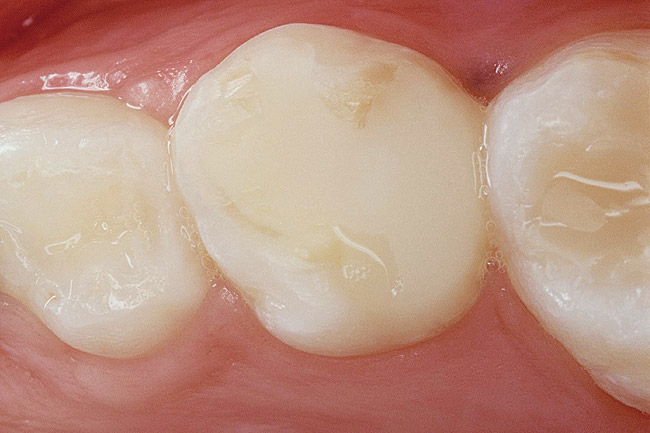

Glass tooth filling cheap, Class I Glass Ionomer Restoration Resurfacing A Pictorial Essay cheap

Class I Glass Ionomer Restoration Resurfacing A Pictorial Essay